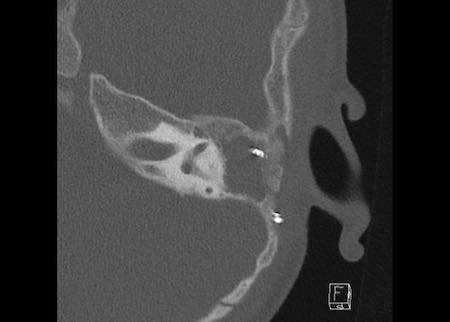

Bên trái là hình ảnh của xương bàn đạp nhân tạo bằng kim loại.

Xương bàn đạp nhân tạo ở vị trí tốt.

Phía trong nằm trong cửa sổ bầu dục, phía ngoài kết nối với mỏm dài của xương đe.